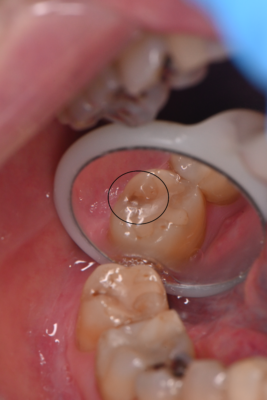

この方は定期的に検診に来ていた方で、検診の際に歯ブラシで違和感があると話をしてくれて確認した所昔詰めたレジンの下から虫歯になっていました。

レジンを除去すると中の方で虫歯になっていました。レジンを外したところはもう元には戻せないので虫歯を完全に除去した後に治療相談をして治療方法をお話しさせて頂きました。

マイクロスコープを使用し少しずつ虫歯を除去して取り残しを防ぎます.その後3Dスキャナーで型どりをします。